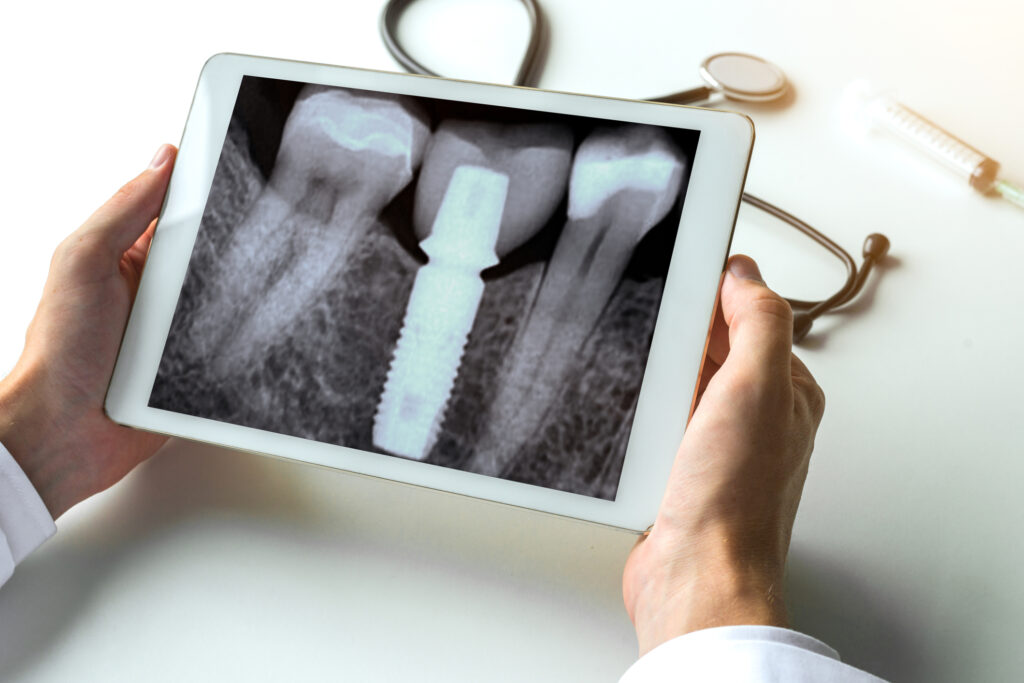

- Evaluare clinică și radiologică

Diferența dintre pivot dentar și implant dentar

| Caracteristică | Pivot dentar | Implant dentar |

|---|---|---|

| Păstrează rădăcina? | Da, se folosește rădăcina naturală | Nu, se înlocuiește complet dintele |

| Necesită tratament de canal? | Da | Nu |

| Indicat după extracție? | Doar uneori (dacă rădăcina rămâne sănătoasă) | Da, este soluția standard |

| Cost | Mai redus | Mai ridicat |

| Timp de vindecare | Mai scurt | Mai lung (3-6 luni cu integrare osoasă) |